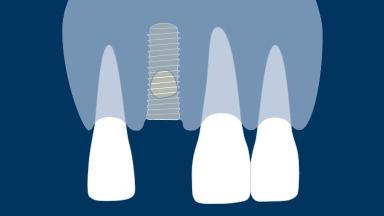

Os pacientes necessitam de tratamento com implantes dentários frequentemente após um evento que causou a extração de um dente ou após um evento traumático que levou à perda do dente. Na maioria dos cenários, o osso alveolar será submetido a reabsorção na região do implante planejado. Considerando que os implantes devem sempre ser instalados em uma posição protética tridimensional ideal, os defeitos peri-implantes nos ossos e tecidos moles são frequentemente encontrados quando os implantes são instalados. Se esses defeitos forem pequenos, eles podem ser tratados no momento da instalação do implante com um alto grau de previsibilidade. Se os defeitos forem grandes, é preferida uma abordagem em etapas, na qual o aumento é realizado primeiro e o implante instalado posteriormente. Este módulo tratará do manejo de defeitos dos tecidos duros e moles peri-implantares resultantes de alterações teciduais pós-extração.